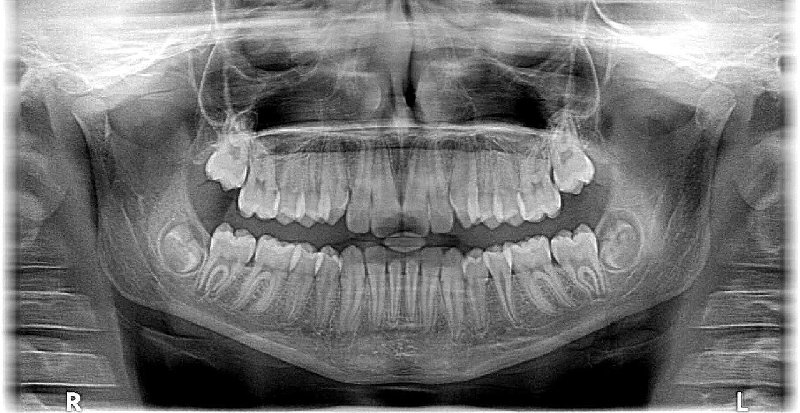

Proces leczenia ortodontycznego zawsze zaczyna się od szczegółowej diagnostyki. Obejmuje ona dokładne badanie jamy ustnej, wykonanie zdjęć rentgenowskich (pantomograficznego i cefalometrycznego), a także pobranie wycisków, na podstawie których tworzy się modele diagnostyczne. Dopiero po analizie wszystkich danych ortodonta jest w stanie stworzyć indywidualny plan leczenia, dostosowany do potrzeb i możliwości pacjenta. Celem jest nie tylko wyprostowanie zębów, ale także uzyskanie prawidłowego zgryzu i harmonii rysów twarzy.